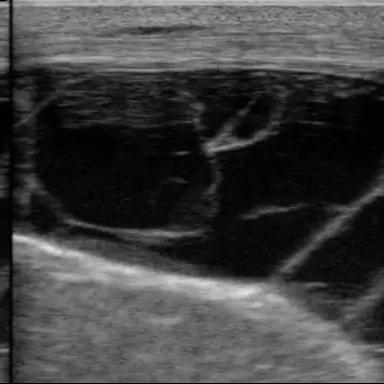

Интерактив по УЗИ!)

313

Всем доброго времени суток!

Сегодня без постов и знаний, просто предлагаю Вам угадать , какой орган визуализирован на снимке!)

Подсказки - это КРС, мясное направление, ...

Чуть чуть мимо, но благодарю за попытку :D

Орган также связан с репродуктивной системой ...

И также есть возможность работы по фертильности самцов, напишу тут чтобы в опроснике не спойлерить) это был снимок семенника у быка породы Ангус)